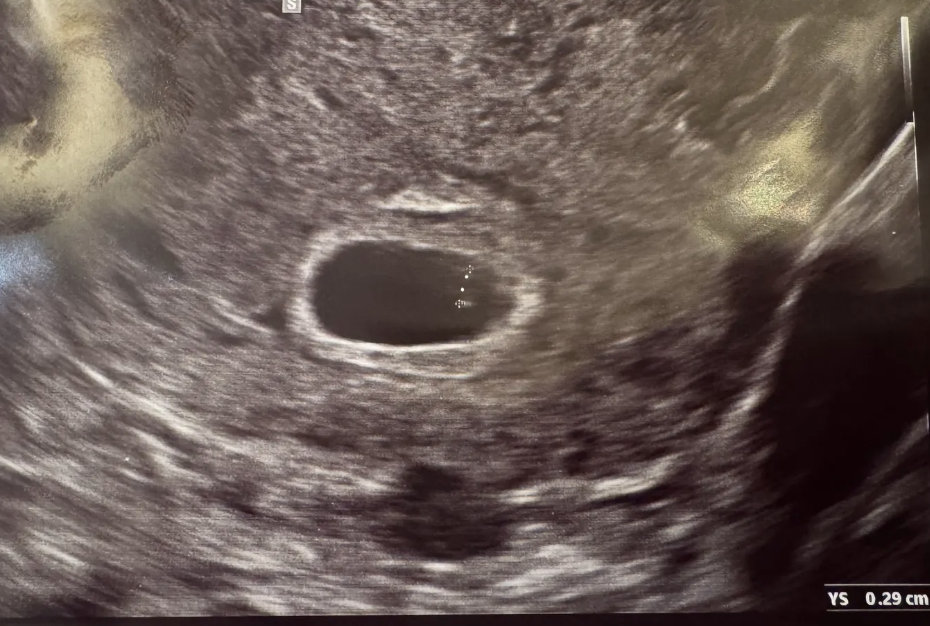

작지만 분명한 생명 0.8cm

“이곳이 난황이구요. 아이 크기는 0.8cm 정도 됩니다”

불과 며칠 사이에 1mm가 자라다니. 잘 크고 있다는 사실이 그저 다행스럽고 감사했다. 다음 진료는 2주 뒤로 예약했다. 그때는 어쩌면 심장소리도 들을 수 있을거라고 했다. 이렇게 작은 생명에게서 심장이 뛴다니. 내 심장도 같이 뛰었다.